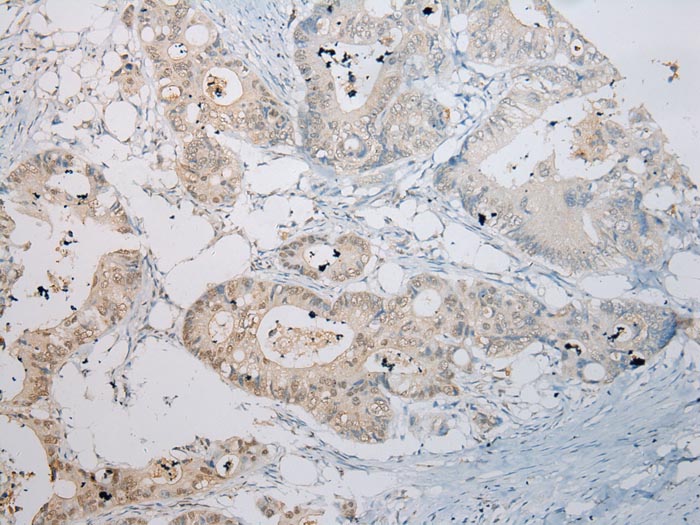

分类: 科研抗体货号: P42998别名: RASSF5应用: IHC反应种属: Human